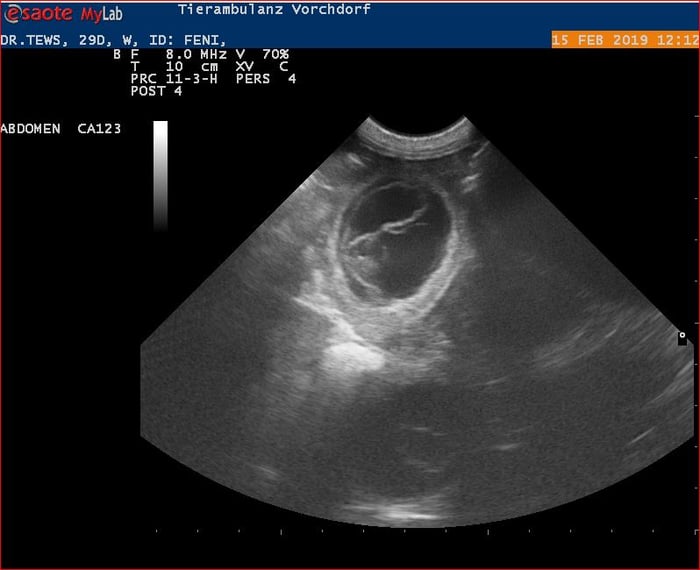

19. Februar 2019

Nun ist die Trächtigkeit von Feni bestätigt und wir erwarten die Welpen rund um

den 20. März.